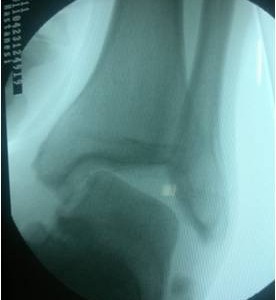

Kırık ve Çıkıklar

ÇIKIKLAR Direkt veya end...

KIRIKLAR ve ÇIKIKLAR

KIRIKLAR ve ÇIKIKLAR KIR...